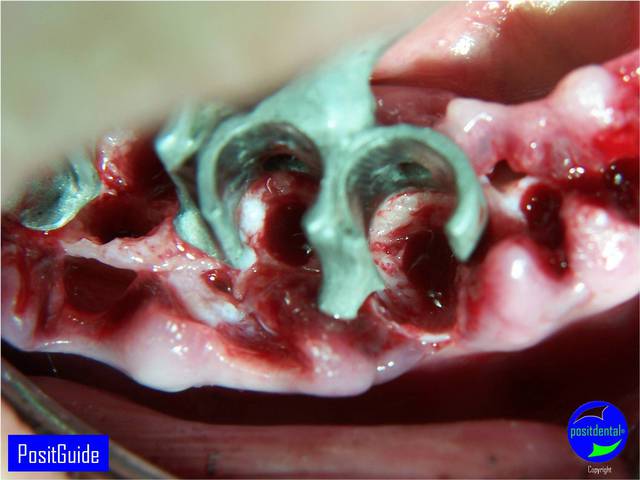

Mise en Charge Immédiate Post Extractionnelle , MCIPE partie chirurgicale de A à Z

implants in situ et S.I.A.O pré-opératoire